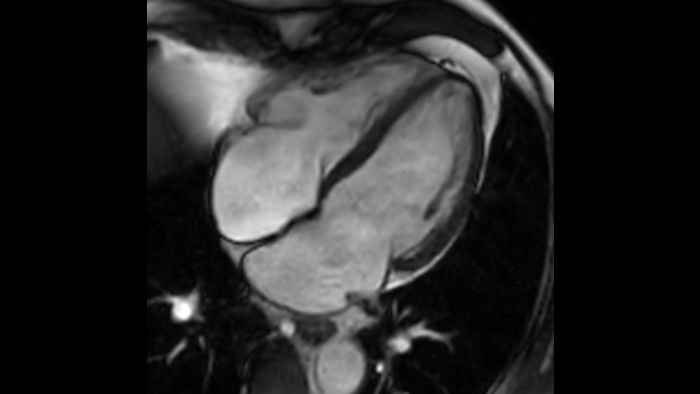

The new reality for your MR imaging

Now you can have it all with the Ingenia Ambition. It offers opportunities to improve your MR imaging at every level.

SmartSpeed SmartSpeed AI enables to decrease the scan time up to 65% with equal or better image quality

Speed & Comfort Provide up to 40% reduction in breath holds, with virtually equal image quality4.

Customer story

Learn how MCVI boosts MRI quality.

Customer story

A leap in pediatric MRI confidence at Altona Children’s Hospital.